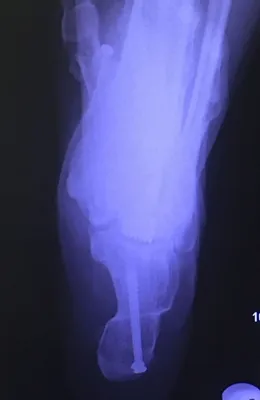

Below are x-rays of a foot pre-operatively (left) where the black line indicates and plantarflexed (downward directed) talus bone and post-surgical repair with a subtalar joint implant and lenthening of the calf muscle which allows the calcaneus (heel bone) to set underneath the talus and the implant keeps the talus from subluxing off the calcaneus and now the talus is more inline with the front of the foot (right).